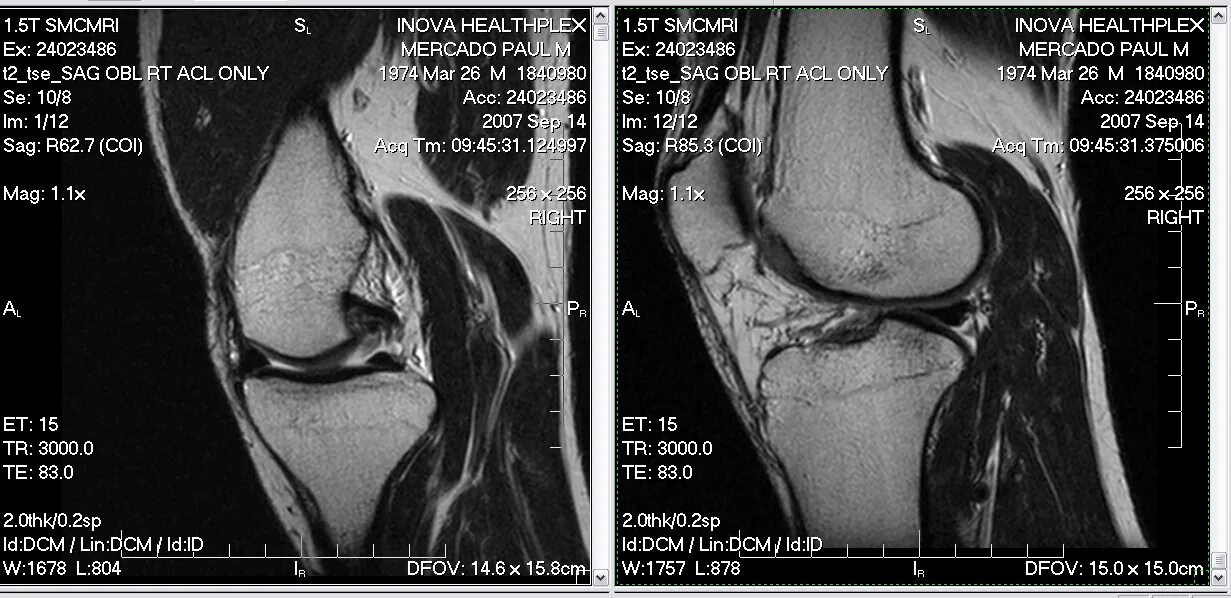

Мрт коленного сустава одежда